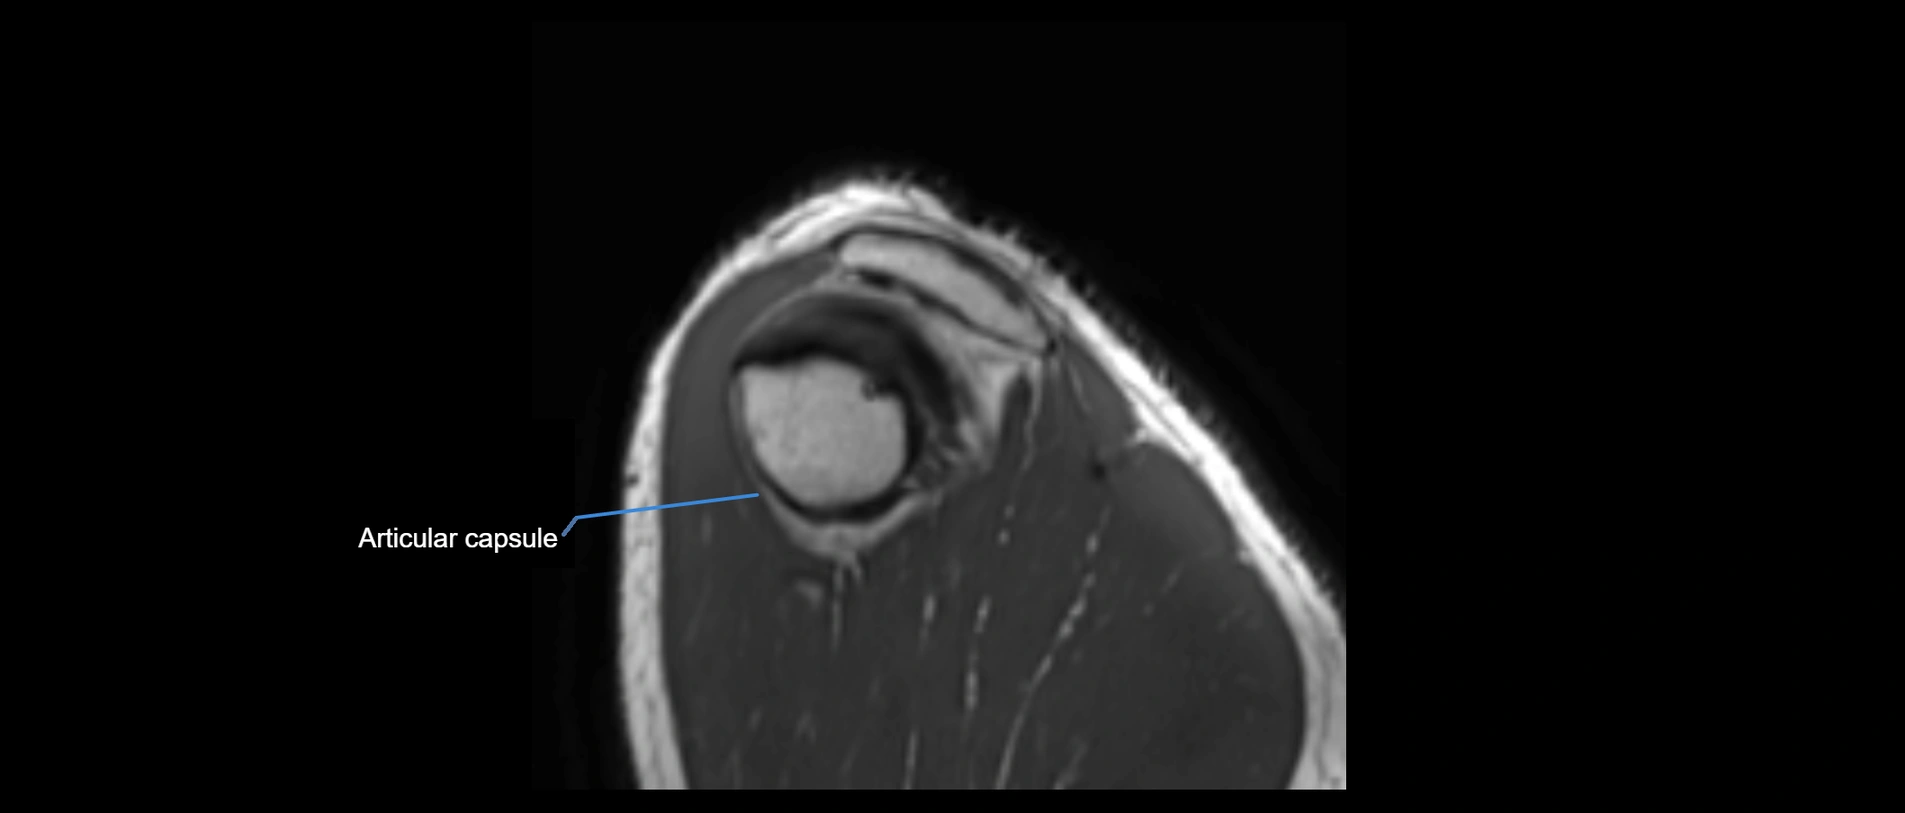

MRI images

image

• Proton Density Fat-Saturated (PD FS):

• Normal ligament: Low signal, uniform thickness.

• Partial tear or sprain: Bright signal or contour irregularity.

• Complete tear: Clear discontinuity with bright signal gap and joint effusion.

• Excellent for assessing joint capsule, coracoclavicular ligaments, and periarticular edema.